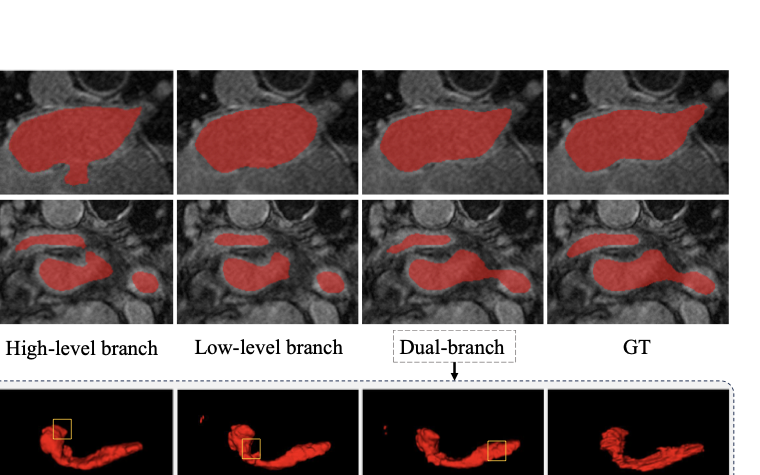

Table [tab:LA_result_table] presents a comparison of our method with other state-of-the-art approaches on the LA dataset. We evaluate our method on the V-Net using 10% and 20% labeled data as well as fully supervised data. With only 10% labeled data at hand, our model exhibits noteworthy enhancements over DTC . Specifically, we achieve improvements of 2.11% and 3.16% in Dice and Jaccard scores, respectively. When 20% labeled data is available, our method achieves a 1.70% improvement in Dice and a 2.81% improvement in Jaccard compared to MC-Net+. Notably, our approach even outperforms the fully supervised results obtained on V-Net. Based on the visualizations in Fig. 6, the first and second rows demonstrate that with only 20% labeled data, other baseline models exhibit fragmentation or missing portions in the challenging areas. In contrast, our method achieves comprehensive segmentation in these challenging regions.

Performance on Pancreas-CT Dataset

Table [tab:Pancreas_result_table] presents a comparison of our method with other state-of-the-art techniques on the Pancreas-CT dataset. When the labeled data is limited to only 10%, SASNet achieves significant improvements compared to other methods. Specifically, our method outperforms URPC in Dice score by 2.85% and in Jaccard by 3.40%. As the percentage of labeled data increased to 20%, our method outperforms URPC in Dice score by 1.58% and in Jaccard score by 2.09%. The third and fourth rows of Fig. 6 illustrate the visual results on the Pancreas-CT dataset with 20% labeled data, other methods tend to misclassify background as foreground. In contrast, our method effectively addresses this issue and accurately segments the target.